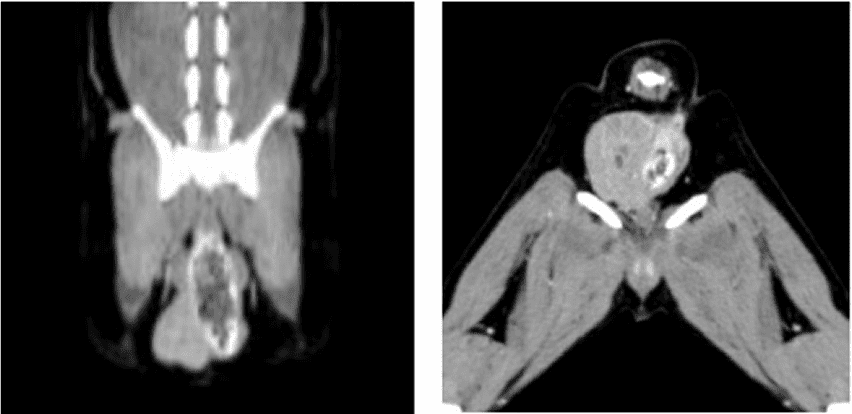

肛門嚢アポクリン腺癌

骨腫瘍